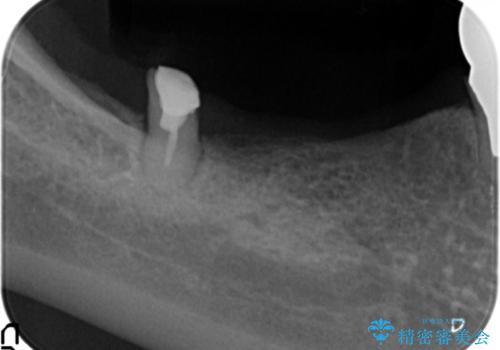

狭小な歯槽骨に対するインプラント治療

- 歯を失い噛めないこと、骨の幅が狭く他院でインプラント治療が難しいと断られ、当院でのインプラント治療が可能かどうか相談来院されました。

骨の造成、角化歯肉の移植を行いインプラント周囲の環境を整えた治療を計画します。